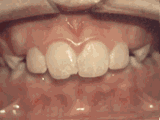

爱美之心,人皆有之~~5月份世界正畸日即将来临,暑假还远吗?分院提前给爱美的你准备好一份大大的福利,还等什么呢?抓紧约起来吧! 发现自己牙齿不整齐影响交际, 怎么还能与小伙伴愉快地玩耍? 无论是即将迈入新的年级还是即将面临找工作, 发现自己是“地包天”“龅牙妹”, 分分钟拉远自己和同龄人的距离! 这些难以启齿的牙齿问题, 想想就让人心碎,怎么办呢? 不要着急,不要慌乱! 这个时候, 你可能需要的就是牙齿矫正了~! 以下图片告诉你, 这些情况都适合去做牙齿矫正哦~! 前牙移位 症状表现:牙齿缺失、牙周疾病等导致相邻牙齿无秩序前突 牙列拥挤 症状表现:牙齿过多,牙槽骨过窄,使牙齿没有足够空间生长造成牙齿排列不齐 开颌 症状表现:通俗来讲就是咬牙时无法紧闭,上下牙齿中间有缝 上牙深覆合 症状表现:上牙边沿覆盖下牙超过1/3,俗话说的天包地 后天牙列稀疏 症状表现:疾病外因等造成的牙列稀疏,牙槽骨过长或牙齿缺失,导致排列太宽松,零零散散 前牙反合 症状表现:下牙边沿覆盖上牙超过1/3,俗话说的地包天 天生牙列稀疏 症状表现:天生的牙列稀疏,牙槽骨过长,牙缝过宽、牙齿较少(一般不缺牙),导致排列宽松,零零散散 以上几种情况有你么? 要知道一口整齐的牙齿 绝对能够把整体的颜值提升N个档次! 如果你不幸中招, 就好好利用这个正畸月, 来分院加入到正畸大军里吧! 牙齿正畸也叫做牙齿矫正,原理简单来讲呢,就是对牙齿施加一个合适的外力(一般通过矫正器来施加),这个力会通过牙齿传递到牙齿周围的牙槽骨上,使得代谢很活跃的牙槽骨发生改建,从而带动牙齿一起缓慢移动。其治疗效果有着肉眼可见的强大变化! 借此正畸月,分院为大家准备了正畸月大放价,暑假提前约的活动!!!如果还想了解更多关于牙齿矫正的信息,欢迎大家来到分院进行咨询哦~我们的专业团队会帮您定制最适合自己的矫正方案,活动月矫正方案免费送哦!定能助您改“斜”归“正”!露出灿烂自信的笑容!